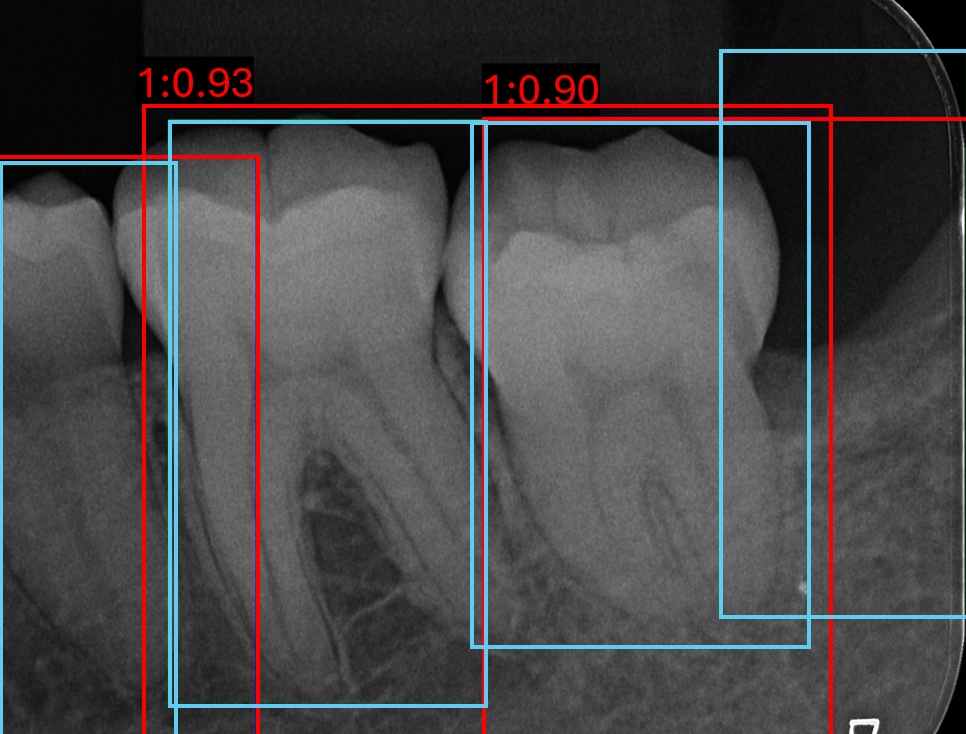

Figure 7 shows qualitative examples of detection performance on the validation set. Both models generally localise tooth boundaries with high precision, although analysing RTMDet performance indicates occasionally grouping of multiple teeth within a single bounding box, while still often retaining the appropriate number of boxes per tooth in the image. In some cases, both methods detect teeth absent from the annotations, suggesting improved actual sensitivity relative to the ground truth but at the cost of reduced quantitative precision.

Refer to caption

(a) Image 119 YOLOv8

(b) Image 120 YOLOv8

(c) Image 171 YOLOv8

(d) Image 119 RTMDet

(e) Image 120 RTMDet

(f) Image 171 RTMDet

Figure 7: Six validation images with overlaid bounding box results, where light blue is the target boxes and red is the predicted boxes.

Both models consistently fail on PLS classes, despite its higher sample size compared to ARR and triple root classes, shown in Figure 7(b) and Figure 7(e). This limitation is likely due to the visual similarity between healthy and widened PLS cases, indicative of a more challenging detection problem. In contrast, ARR and triple root teeth exhibit richer and more distinctive features, leading to stronger performance overall. However, false negative predictions for ARR remain evident throughout, in Figure 7(c) and Figure 7(f).